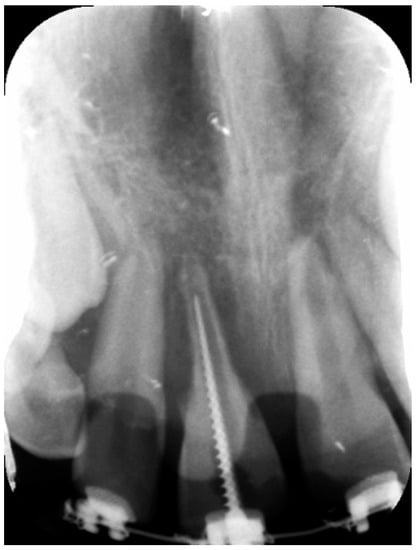

2. Case Report